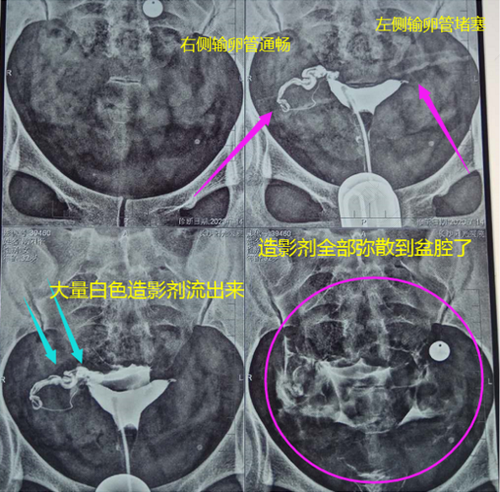

2、很多消化系统和泌尿方面的疾病,都需要造影来进行检测,这样可以让医生更直观和清晰的对病情进行了解,对一些特殊的造影术,还是有一定要求的,比如说输卵管的造影,就要求女性在一个月之内,不能过夫妻的生活,同时要多喝水,加强运动。